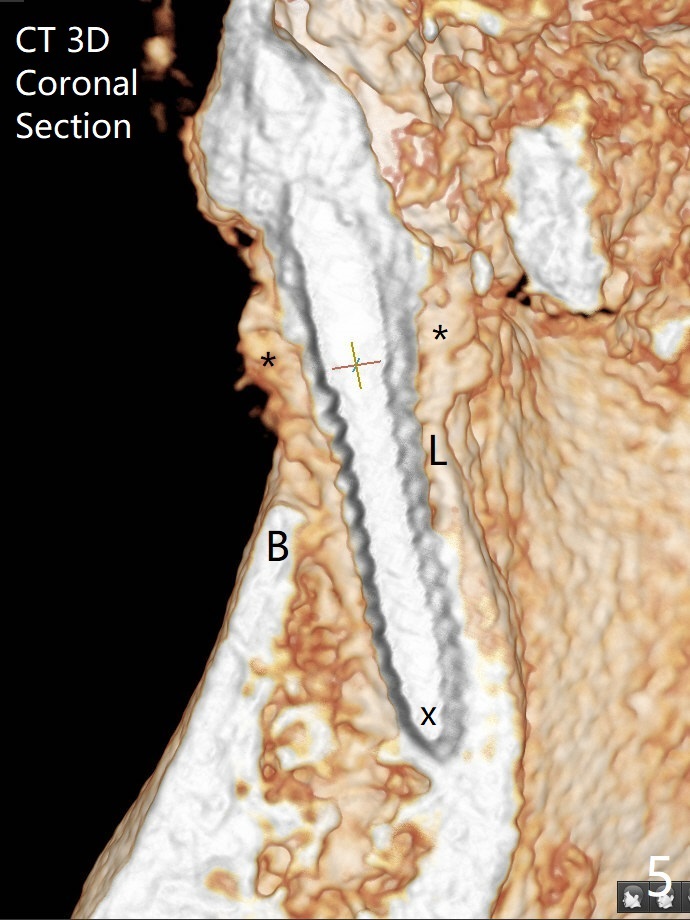

After extraction of the tooth #24 with vertical root fracture (loss of buccolingual plates), osteotomy is initiated with 1.2 mm drill free hand; the trajectory seems satisfactory (Fig.1). With sequential osteotomy, a 2.5x14(2) mm 1-piece implant has difficulty being placed deep (Fig.2), apparently associated with dense bone. Allograft is placed not only mesiodistal (Fig.2,4 *), but also buccolingual (Fig.3,5,6 *) to cover the exposed implant threads. In fact inability to place the implant deep is due to the apex of the implant (Fig.5,6 x) touching the lingual (L) cortical plate. If surgical guide were used, the implant placement difficulty would not occur. The surgery would be shorter and easier. The seemingly easiest implant placement should be assisted with a guide! In addition, preop CT would dictate implant placement in the middle of the socket buccolingual. The lingual (Fig.7 *) and buccal (Fig.8 <) gingiva remains bulky, although asymptomatic, 8 days postop.